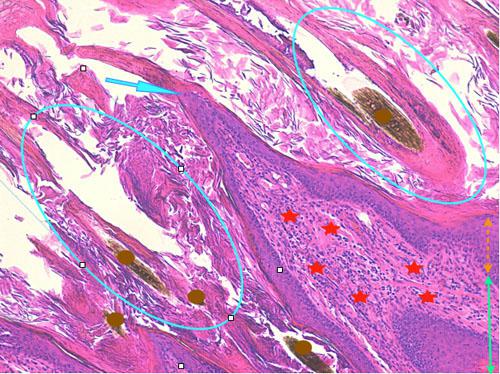

Légendes de la Photo 11 :

- Flèche turquoise : projection papillaire de l’épiderme hyperplasique se formant à la marge d’un ostium folliculaire

- Ronds marrons : tiges pilaires

- Ovales turquoises vides : follicules pileux, infundibula hyperkératosiques (orthokératose)

- Double flèche orange : épiderme (portion non kératinisée)

- Double flèche verte : derme

- Étoiles rouges : infiltrat inflammatoire dermique péri-vasculaire

Photo 12 (Hémalun-Eosine X100): vue rapprochée d’une papille ostiale.

Elle est revêtue d’un chapeau parakératosique au sein duquel les kératinocytes sous-cornés sont vacuolisés.

Légendes de la Photo 12 :

- Flèche truquoie : sommet d’une projection papillaire de l’épiderme hyperplasique se formant à la marge d’un ostium folliculaire

- Double flèche orange pointillée : épiderme (portion non kératinisée)

- Rond marron : tige pilaire

- Ovales turquoises : infundibula folliculaires hyperkératosiques (orthokératose)

- Flèche jaune : parakératose coiffant la papille épidermique

- Etroile rouge vide : le sommet de la paille épidermique montre une ballonisation des kératinocytes